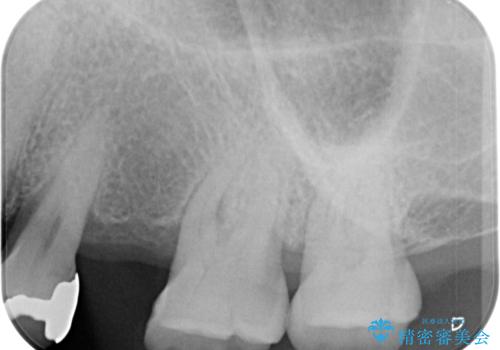

事前に仮歯を用意し、インプラント埋入時に仮歯を装着し、その後歯肉の治りを待って速やかにオールセラミッククラウンにて補綴治療を行うこととしました。

インプラント埋入時に十分な安定性が確認できたため、当日仮歯を装着しました。

埋入から2ヶ月ほどでインプラントの十分な生着が認められ、処置した歯肉も綺麗に治癒したため、速やかに補綴治療を行いました。